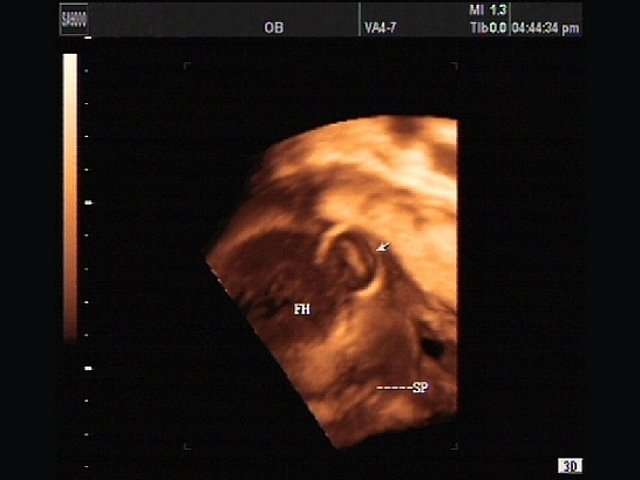

- Система Live 3D - возможность проведения трехмерного УЗИ в реальном времени (4D):

- 3D датчики;

- получение любого среза в каждой из 3-х проекций;

- получение трехмерных изображений в режиме серой шкалы, а также цветного и энергетического допплера;

Объемный датчик 3D 4-8ET/40/84

Трехмерные абдоминальные исследования, акушерство (трехмерное УЗИ плода) и гинекология.

Биопсийный набор: есть.

Объемный датчик VAW 4-7/40/69